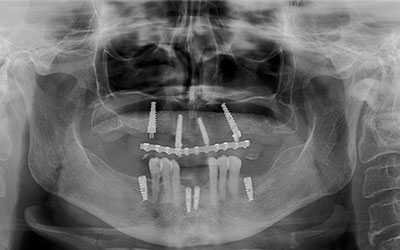

La prótesis dental híbrida es una estructura fija atornillada sobre implantes dentales que tiene como objetivo reponer las piezas dentales y tejidos blandos -encía- perdidos.

La prótesis dental híbrida consta de una estructura de metal recubierta de varias capas de porcelana blanca y rosa que dan la estética de los dientes y de la encía.

Dicha estructura se atornilla sobre los implantes que se han colocado previamente en el hueso mediante la cirugía.

Esto se hace mediante unos tornillos intermedios que fijan toda la estructura y sellan el espacio entre la prótesis y los implantes.

Por último, la entrada de estos tornillos a través de la prótesis se sella mediante el uso de teflón y resina, como si se estuviera realizando una obturación o empaste dental.